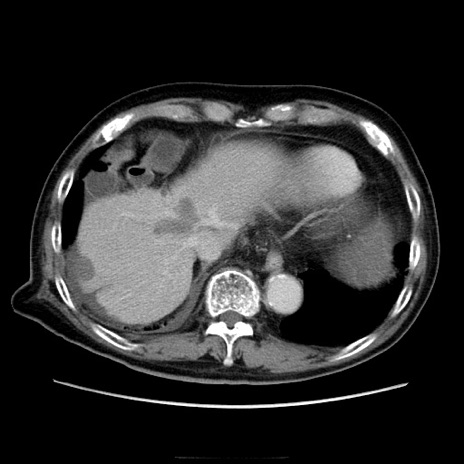

症例21(横断像)

【症例】70歳代男性

【主訴】腹痛

【現病歴】肝硬変・肝細胞癌にてかかりつけの方。約9時間前に食後より腹痛出現。症状が徐々に増悪し、嘔吐出現したため来院。

【既往歴】肝硬変、肝細胞癌(RFA、TACE後)

【身体所見】意識清明、表情苦悶様、BT 36℃、BP 129/78mmHg、P 88bpm、SpO2 97%(RA)、右上腹部から心窩部にかけて圧痛あり、反跳痛なし、筋性防御あり。

【データ】WBC 5800、CRP 0.16